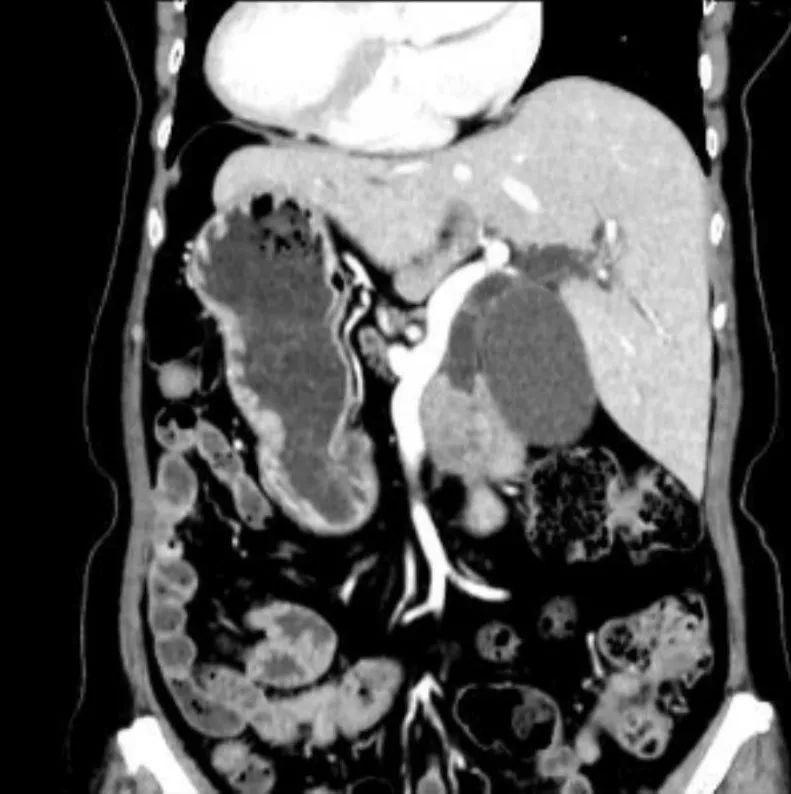

经过相关检查发现,陈阿姨胰腺头部出现了一个直径约 2 cm 的肿瘤,压迫了胰头旁的十二指肠乳头,十二指肠乳头是胆管及胰管的开口,是胆汁及胰液排出的必经之路。

陈阿姨的皮肤黄染正是由于这个「肿瘤」的捣乱,从而导致胆汁无法排入肠道引发的梗阻性黄疸。综合陈阿姨各项临床检查,主要诊断考虑为胰腺癌。

然而更加棘手的是,各项检查提示,陈阿姨是一名发生率约为百万分之一的心肝脾胃肠等内脏位置 180 度反位的 「镜像人」。为「镜面人」实施如此复杂的手术更是难上加难。

外科医生手术操作习惯和思维模式是在正常解剖的基础上培养出来的,患者胸腹脏器完全反位,其解剖与正常解剖完全相反,所以手术中主刀医生的手术站位与常规完全相反。